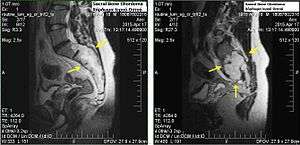

Chordomas can arise from bone in the skull base and anywhere along the spine. The two most common locations are cranially at the clivus and in the sacrum at the bottom of the spine.[1]